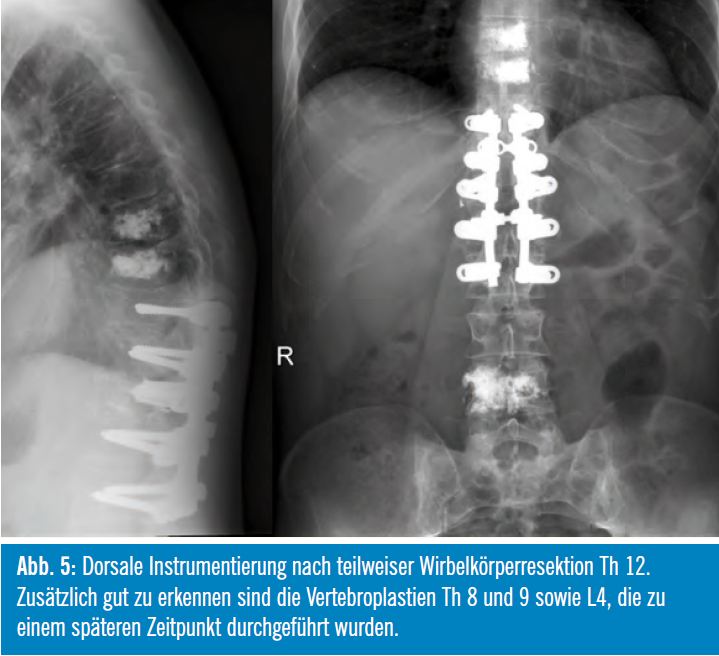

Da es sich durch die Wirbelkörperfraktur ventral und die dorsale operative Dekompression so gut wie immer um eine mechanisch instabile Situation an der Wirbelsäule handelt, ist meist eine zusätzliche Instrumentierung erforderlich, die in der Regel als dorsale Spondylodese 2 Segmente cranial und caudal der Läsion ausgeführt wird (Abb. 5). Bei bestimmten Indikationen kann auch die Dekompression und Instrumentierung von ventral erfolgen, wobei meist zusätzlich ein Wirbelkörperersatz oder Titan Cage implantiert wird.